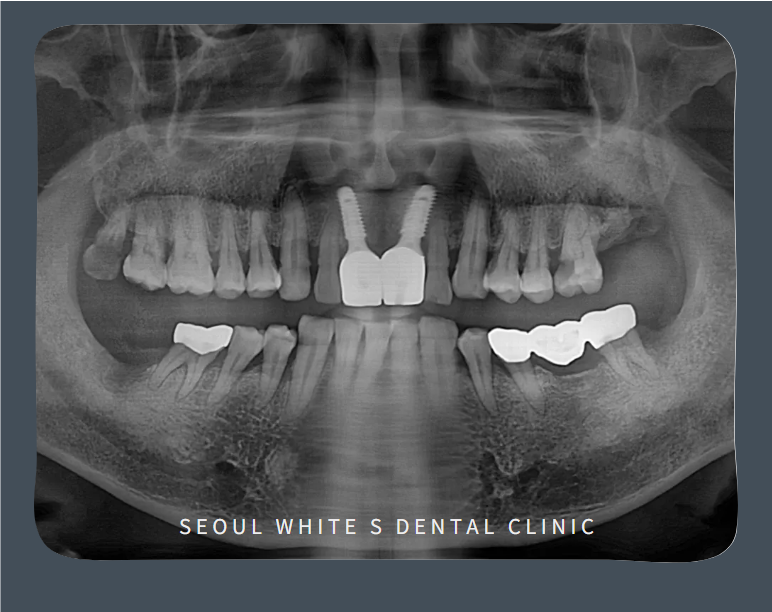

발치 후 당일 임플란트 식립과 즉시 임시치아를 제작해 드렸어요!

그리고 임플란트가 잇몸뼈에 잘 고정될 수 있도록 충분한 시간을 기다려준 후, 크라운(보철물)을 올리는 보철과정을 진행해 주었습니다.

최종 보철물이 완성된 모습입니다!

눈에 가장 잘 띄는 앞니기 때문에 신경을 많이 쓰고 계셨는데 임시치아를 사용하는 동안에도 불편함이 없었고 최종 보철물까지 단단하고 예쁘게 제작되어 영도치과 서울화이트S치과에 너무 감사하다고 말씀 주셨어요:)

그리고, 우식과 치주 질환으로 불편하셨던 오른쪽 아래 끝 어금니와 왼쪽 위아래 어금니 발치도 깔끔하게 도와드렸습니다.